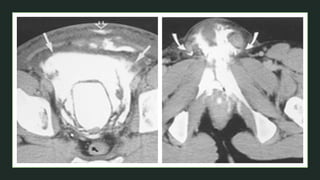

• #39 Axial T2 Axial T1+C FS An extravesical mass (arrows) involving the pelvic wall and cervix

• #40 85 year old man complains with hematuria CT IVP shows Solid enhancing mass arising from the right posterior bladder wall above the level of the right vesicoureteral junction and, although it has a bulging of the external bladder contour, does not extend into the surrounding fat planes. No enlarged lymph nodes seen, only a single 7.0 mm lymph node adjacent to the right common iliac vessels. The kidneys are normal in appearance, with no calculi, or hydronephrosis. There is a 4.0 cm cortical cyst in the right middle third that shows a few thin septations and calcifications (Bosniak II). The collecting systems are unremarkable, with no filling defects or strictures are identified. The remainder imaged solid and hollow abdominal viscera are normal in appearances. Imaging features are consistent with a bladder tumor, most likely a transitional cell carcinoma.  The patient was submitted to a transurethral resection of the bladder tumor (TURBT).